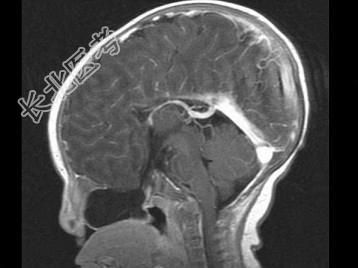

- 单项选择题两个月女婴,口咽部有一肿块, 行CT检查如图,请选择最可能的诊断 ( )

A、脑积水

B、胼胝体发育不全

C、透明隔囊肿

D、前脑无裂畸形

E、Dandy-Walker综合征